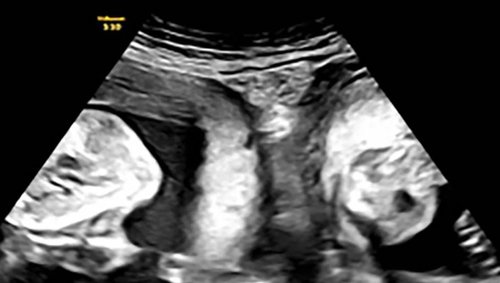

Prema bolnici, novopečena je majka rođena s dva grlića maternice i dvije maternice, stanje koje se naziva didelfija maternice koje se nalazi u otprilike 1 od 2000 žena.

Ali u januaru Li je ponovno zatrudnjela i otkrila je tokom ranog ultrazvuka da ne očekuje samo jedno dijete već blizance - po jednog u svakoj maternici.